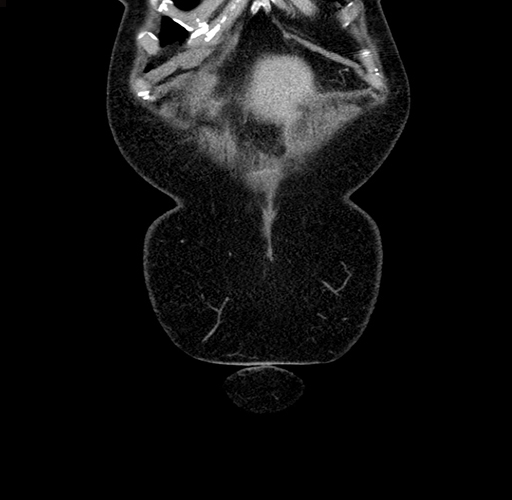

Coronal Venous